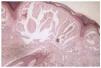

En ambos casos se tomó muestra para examen histopatológico, el cual mostró la existencia de una epidermis atrófica con masas redondeadas, homogéneas y fisuradas de material coloide en dermis papilar, con intensa elastosis solar (fig. 3).

FIG. 3.--Masas redondeadas, homogéneas y fisuradas de material coloide en dermis papilar, separadas de la epidermis por una franja de dermis normal (zona Grenz o límite).

Al microscopio óptico, se aprecia una masa homogénea, eosinófila, fisurada, en dermis papilar y reticular separada de la epidermis por una banda de dermis normal, la denominada zona Grenz (o límite)8. En la variedad nodular puede llegar a ocupar todo el espesor dérmico. En la forma juvenil las masas de coloide pueden llegar a invadir epidermis y pueden apreciarse cuerpos de Civatte sin llevar aparejada la elastosis característica de la forma adulta9. Se observan folículos pilosos y glándulas sebáceas que no suelen estar infiltradas por este material. El material coloide, como el amiloide, es PAS+ y muestra birrefringencia con la tinción rojo congo. La diferencia fundamental es la existencia de filamentos ondulados de las escleroproteínas producidas por los fibroblastos. El grosor de estos filamentos es mayor en la forma adulta que en la forma juvenil10.